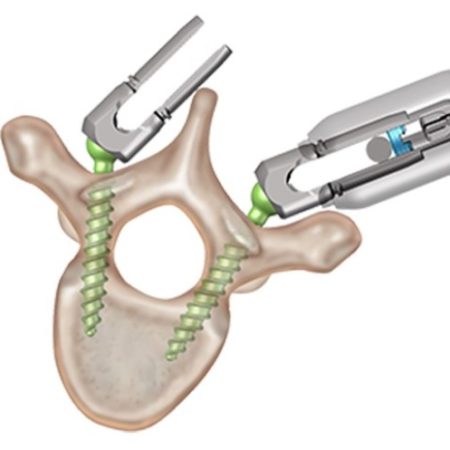

EXPEDIUM VERSE